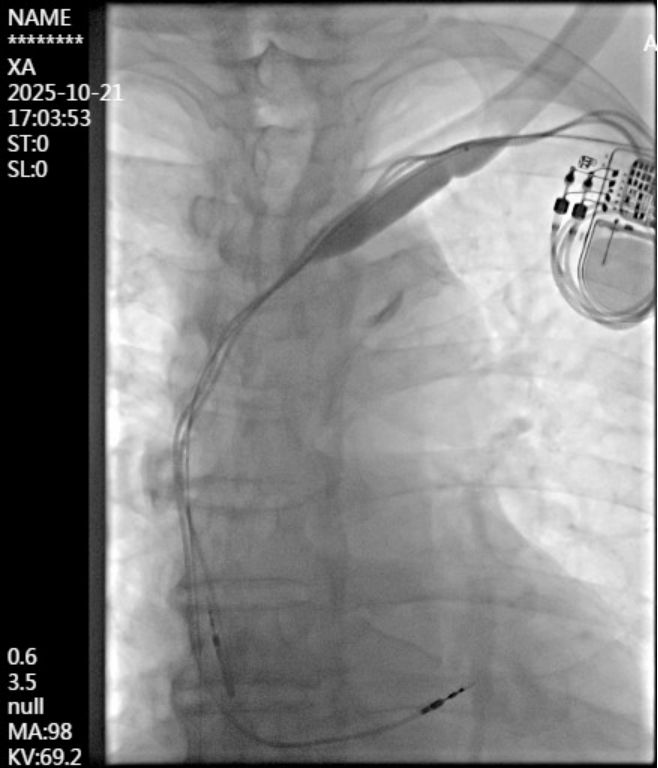

手术团队选取左上臂肱动脉-贵要静脉内瘘的贵要静脉段,距肘关节3cm处为穿刺点,置入血管鞘管。DSA造影显示左侧头臂静脉(无名静脉)闭塞,周围大量侧支循环开放,锁骨下静脉及腋静脉未见狭窄。术中,经造影导管置入0.035英寸超滑导丝,在闭塞处受阻,后更换为0.018英寸导丝,在造影导管引导下成功通过闭塞段,进入上腔静脉并送达下腔静脉。随后更换加硬导丝,以不同型号球囊由小到大逐级、缓慢扩张左侧头臂静脉及与上腔静脉交汇处,最终成功解除狭窄。术后DSA显示左头臂静脉恢复通畅,侧支血管影消失,全程起搏器功能正常。

成功开通闭塞的左侧头臂静脉,全程心脏起搏器功能良好。